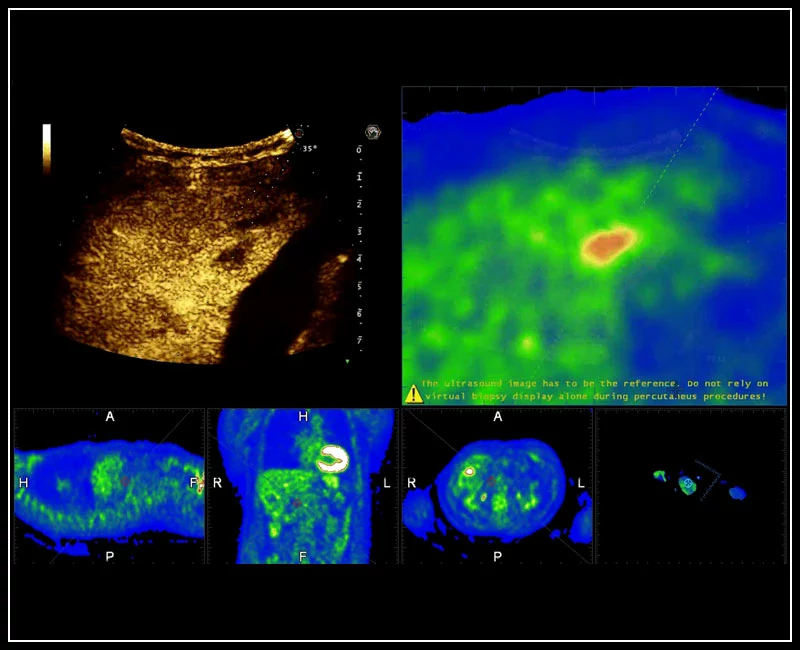

MyLab™9 Platform - Precise lesion detection and guidance with Virtual Biopsy

MyLab™9 Platform - Precise lesion detection and guidance with Virtual Biopsy